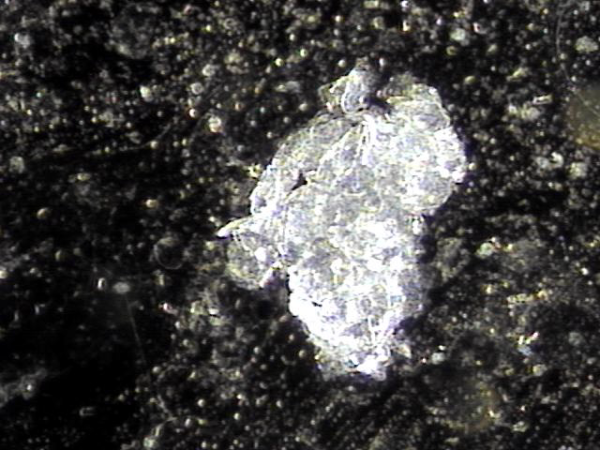

내원당일 전립선의 표적 치료후 배양과 전립선액의 PCR 검사를 위해 채취하고 검사한 현미경학적 확대 사진입니다.

A high-magnification microscopic image taken on the day of the visit, following targeted prostate therapy,

showing the prostatic fluid sample collected for culture and PCR testing.